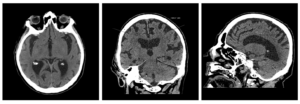

Признаки умеренно выраженной наружная

Признаки умеренно выраженной наружная 113 фото